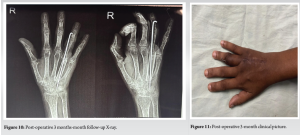

Histological findings (Fig. 8 and 9) confirmed the diagnosis of GCT, demonstrating multinucleated large cells and mononuclear stromal cells. The stromal cells exhibited round, oval, or spindle shapes, characterized by eosinophilic cytoplasm and nuclei containing scattered chromatin. At a 3-month follow-up, the range of motion had reverted to a functional level, with satisfactory graft incorporation, and no additional problems were seen (Fig. 10 and 11). No recurrence was observed during later follow-ups, and the patient attained an acceptable and tolerable range of motion. A routine chest radiograph was performed to exclude metastasis, and no evidence of metastasis was observed in subsequent follow-ups.